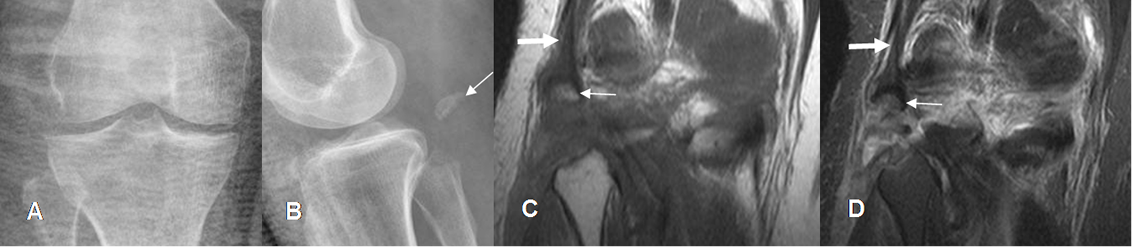

Fig 41. Enfermedad de Osgood Schlatter.

A: Rx lateral, B: RM sagital en T1 y C: RM sagital en STIR. Fragmentación de la espina tibial anterior. (Flechas delgadas). En las imágenes de RM hay cambios inflamatorios en la parte anterior de la tibia y la grasa de hoffa. (Flechas gruesas).